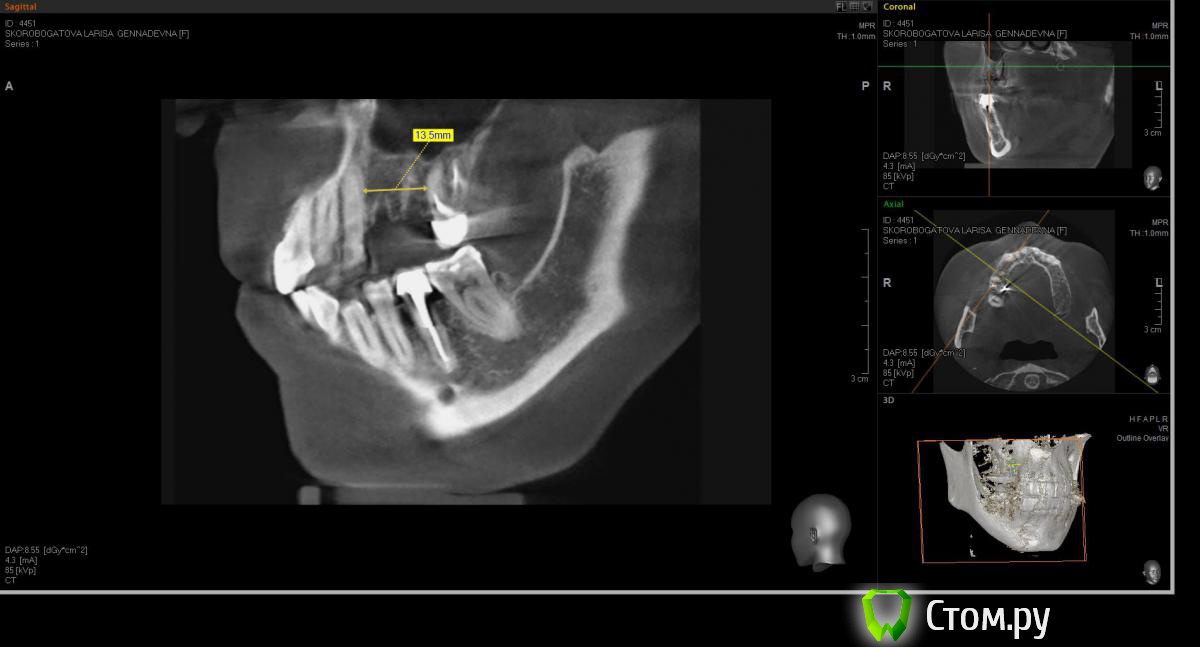

denis1987 Опубликовано 26 марта, 2014 Поделиться Опубликовано 26 марта, 2014 (изменено) У пациентки отсутствуют зубы 14, 15. Согласилась на протезирование с опорой на импланты. Что делать в данном случае ? Расстояния для двух имплантов маловато, а если делать один - то получиться гигантская коронка... Как бы вы поступили в данном кейсе ? Заранее спасибо за советы ! =) Изменено 26 марта, 2014 пользователем denis1987 Ссылка на комментарий

Sahan Опубликовано 26 марта, 2014 Поделиться Опубликовано 26 марта, 2014 Для двух 3,5 мм места впритык. 1 Ссылка на комментарий

ILGAMSA Опубликовано 26 марта, 2014 Поделиться Опубликовано 26 марта, 2014 Фото только что приложил) Давно не заходил на форум , уж забыл как у нас тут и что ) при 13 мм влезают две трешки.А какой системой работаете? Если минимальный диаметр импланта 3.5, то вполне возможно установить один имплант или в проекции четвертого, или пятого, окклюзионно добавить десны, в последующем временной коронкой сформировать овоид, сосочки в проекции консоли. В противном случае эстетики хорошей не будет. 2 Ссылка на комментарий

red_butler Опубликовано 26 марта, 2014 Поделиться Опубликовано 26 марта, 2014 Мне кажется срезы выставлены не правильно, во рту мерили? Ссылка на комментарий

kriokov Опубликовано 26 марта, 2014 Поделиться Опубликовано 26 марта, 2014 Мне кажется срезы выставлены не правильно согласен, видно хорошо контуры лунок отсутствующих зубов, измерено высоковато и срез к небному корню 6.Сделал бы вариант ILGAMSA , один винт дистально, и овоид медиально, ширина там должна быть , не так давно зубы удалили 1 Ссылка на комментарий

j-kost9 Опубликовано 26 марта, 2014 Поделиться Опубликовано 26 марта, 2014 (изменено) 1,5мм+3.5мм+3мм+3,5мм+1,5 мм=13 мм1,5мм от зубов3мм между имплантатами Изменено 26 марта, 2014 пользователем j-kost9 Ссылка на комментарий

CToMaToJlor Опубликовано 26 марта, 2014 Поделиться Опубликовано 26 марта, 2014 (изменено) Влазит два по 3,3. А срезы действительно не очень то ровно выставлены. Если подравнять, то может и меньше 13 получиться. А вообще- такие вьюверы для 3д кт это попытка круглое измерить квадратным( имею в виду программки типа пикасо и как у вас на картинке) предсказуемей программки с дугой (произвольной или стандартной) по которой срезы делаются. Типа сироны или айкат. Изменено 26 марта, 2014 пользователем CToMaToJlor Ссылка на комментарий